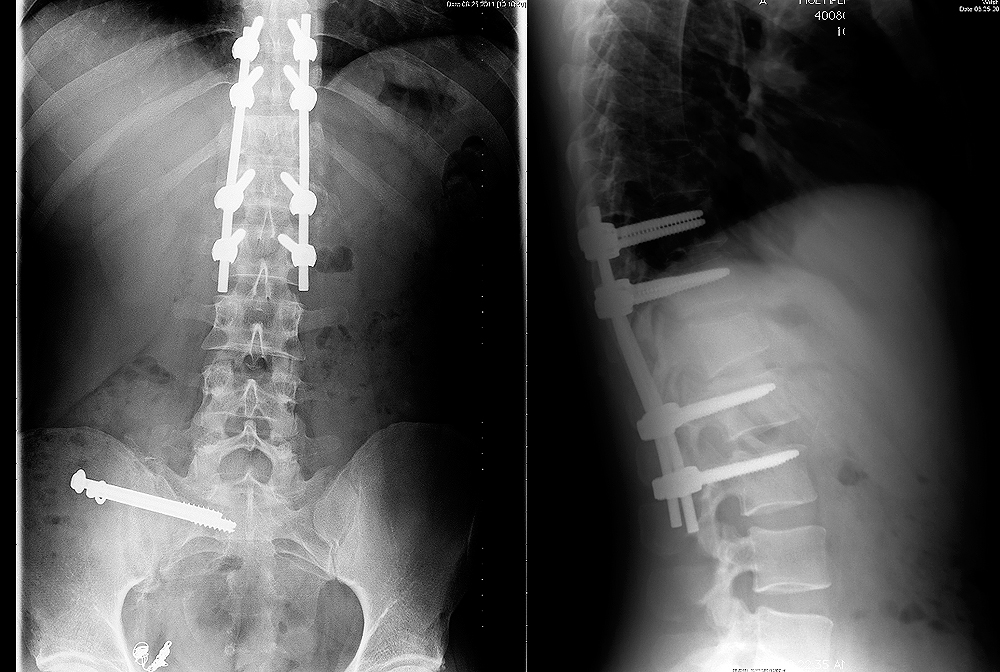

The impact was so harsh that Paul suffered multiple spinal and pelvic fractures, severe internal bleeding and abdominal injuries. He spent 6 days in a coma and another month in the hospital. Doctors performed spinal fusion surgery to 5 levels of his vertebrae. Because of his disability he was let go from his job at SIR Hollywood, and as a result his medical insurance was terminated. With no ability to work he lost his apartment soon after. Paul's hospital bills add up to well over $1 million dollars. The driver not only left Paul with a massive hospital bill, she stole a life's joy from him as he lie broken in the street that day. Paul may never again ride a bicycle. None of the witnesses that stayed managed to get a plate, just a vehicle description.